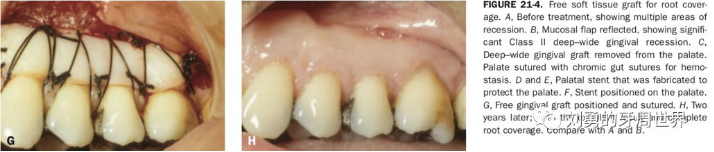

對(duì)于需要進(jìn)行根面覆蓋的手術(shù),移植瓣需要縫合固定到CEJ冠向1mm左右的位置。如下圖: